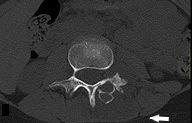

El segundo caso es una mujer de 10 años que consulta por dolor lumbar de predominio nocturno de 4 meses de evolución. No impotencia funcional para la deambulación ni otra sintomatología. A la exploración física, actitud escoliótica por dolor lumbar con leve edema a nivel de L2-L3, resto normal. Ante lumbalgia con datos de alarma (dolor nocturno), se realizan radiografía ósea (Fig. 3) y RM (Figs. 4 y 5) donde se aprecia lesión osteolítica expansiva con nivel líquido en su interior en arco posterior izquierdo de L3, así como edema de médula ósea y partes blandas y tomografía computarizada (TC; Fig. 6) donde se describe lesión lobulada y con margen esclerótico, planteando el mismo diagnóstico diferencial que en el caso anterior. Se realiza resección en bloque de la lesión y se confirma histológicamente el diagnóstico de QOA. Actualmente se encuentra sin clínica y recuperada.

| Figura 6. TC de columna vertebral: lesión osteolítica expansiva y multilobulada en lámina y pedículo vertebrales izquierdos de L3 (flecha) |